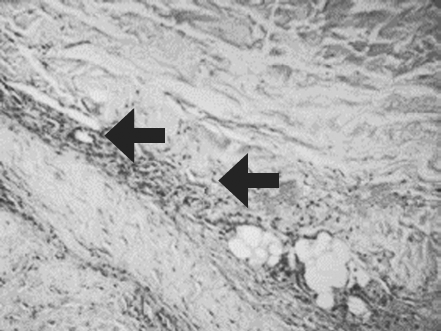

При гистологическом исследовании биоптатов из зоны трансплантации МСК ЖТ констатировано наличие выраженной васкуляризации с перифокальной пролиферацией фибробластов как в поверхностных, так и в глубоких слоях дермы (рис. 6, 7).

Рис. 7. Пациент Д., 49 лет, 5-е сутки наблюдения. Новообразованные сосуды с перифокальной пролиферацией фибробластов. Окраска гематоксилином и эозином. Увеличение ×400

Fig. 7. Patient E., 49 years old, 5th day of observation. Newly formed vessels with perifocal proliferation of fibroblasts. Color in gof hematoxylin-eosin. Zoom ×400